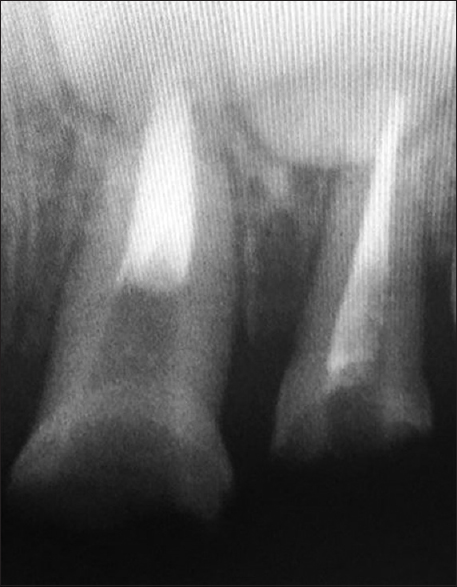

Two-third of the obturation material was removed from the upper left central and lateral incisors [Figure 3]. The trial fit of the endodontic post was done. On confirming the appropriate fit of the post, they were then conditioned with 37% phosphoric acid for 30 s, followed by washing, drying, and applying the adhesive system followed by cementation with resin-reinforced glass-ionomer cement. The shape and shade of the biological post and crown were modified to match the adjacent right central and lateral incisors, respectively. The parents were satisfied with the rehabilitation of the teeth using biological restoration [Figure 4].

thumb

Figure 4: Postoperative clinical Picture